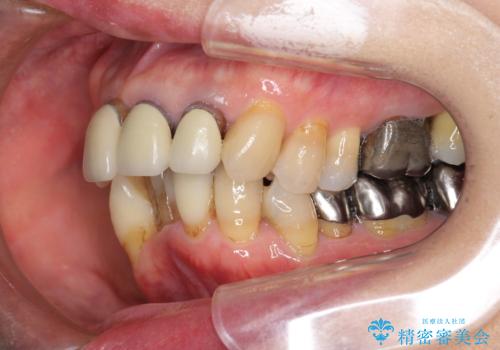

- 上顎前歯の黒ずみの改善、下顎前歯の十度なガタつき、矯正治療とセラミック治療を含む全体的な治療を希望され来院されました。

銀歯を高強度の仮歯に替えたのち、下顎前歯のみの部分矯正→全体的なマウスピース矯正治療(インビザライン)→最終的なセラミック治療と治療を進めます。

矯正治療と目立つ銀歯のやりかえを行ったことでかみあわせだけでなく、審美性・清掃性も改善し口腔内の環境を劇的に改善することができました。